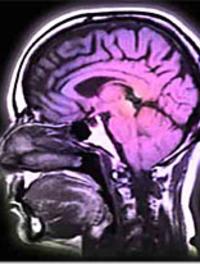

L’acide tranexamique après une hémorragie cérébrale, à administrer plus tôt ?

Le pronostic des hémorragies intracrâniennes est grevé par une mortalité élevée (40 % après 1 mois) mais aussi par des séquelles handicapantes [...]

La migraine peut affecter jusqu' à 15 % de la population générale. Une étude précédente, dénommée Camera-1 (Cerebral Abnormalities [...]

Les stratégies diagnostique et thérapeutique dans la sclérose en plaques (SEP) ont changé au cours des 5 dernières années. Plusieurs [...]